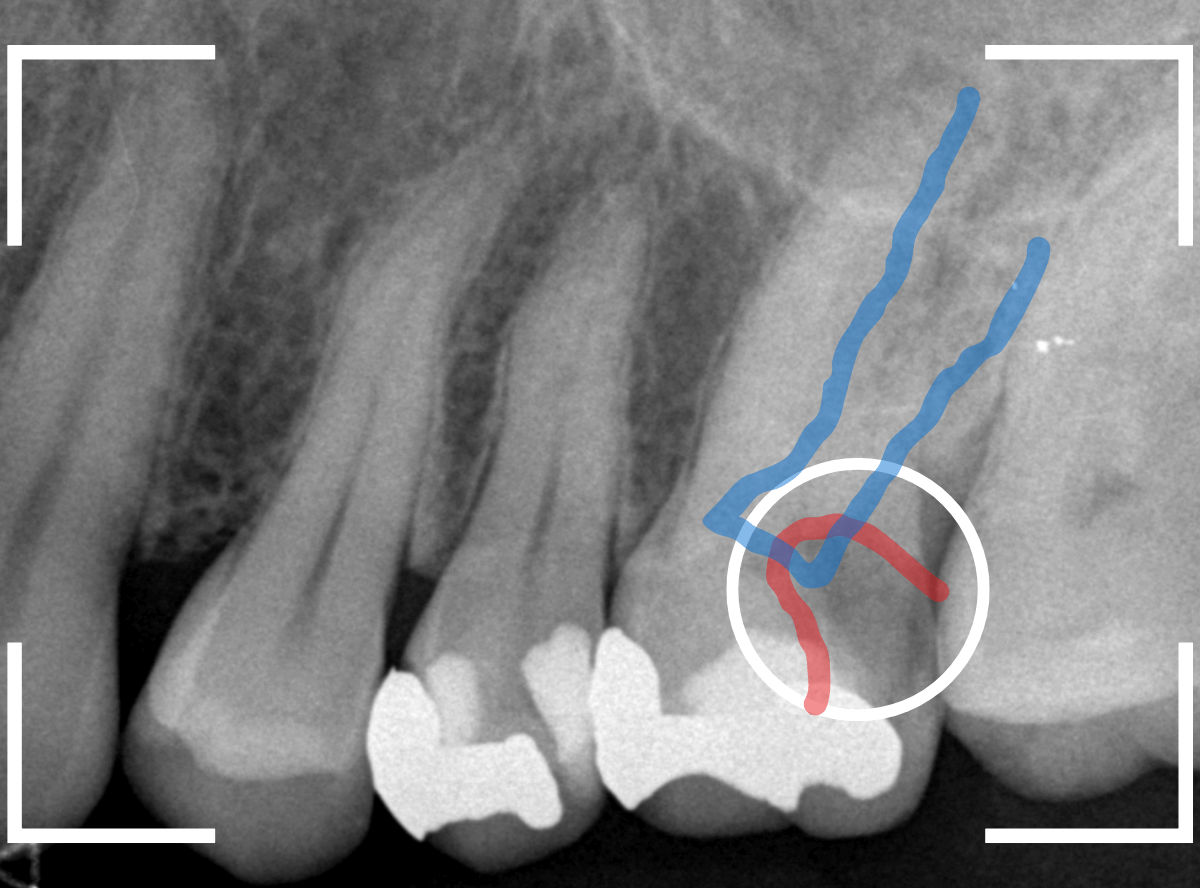

今回は、奥歯が神経に達する虫歯になってしまった患者さんのケースです。

レントゲン写真で確認します。

金属のつめものの下が、神経まで達する大きな虫歯になっています。

麻酔をして神経の治療をします。